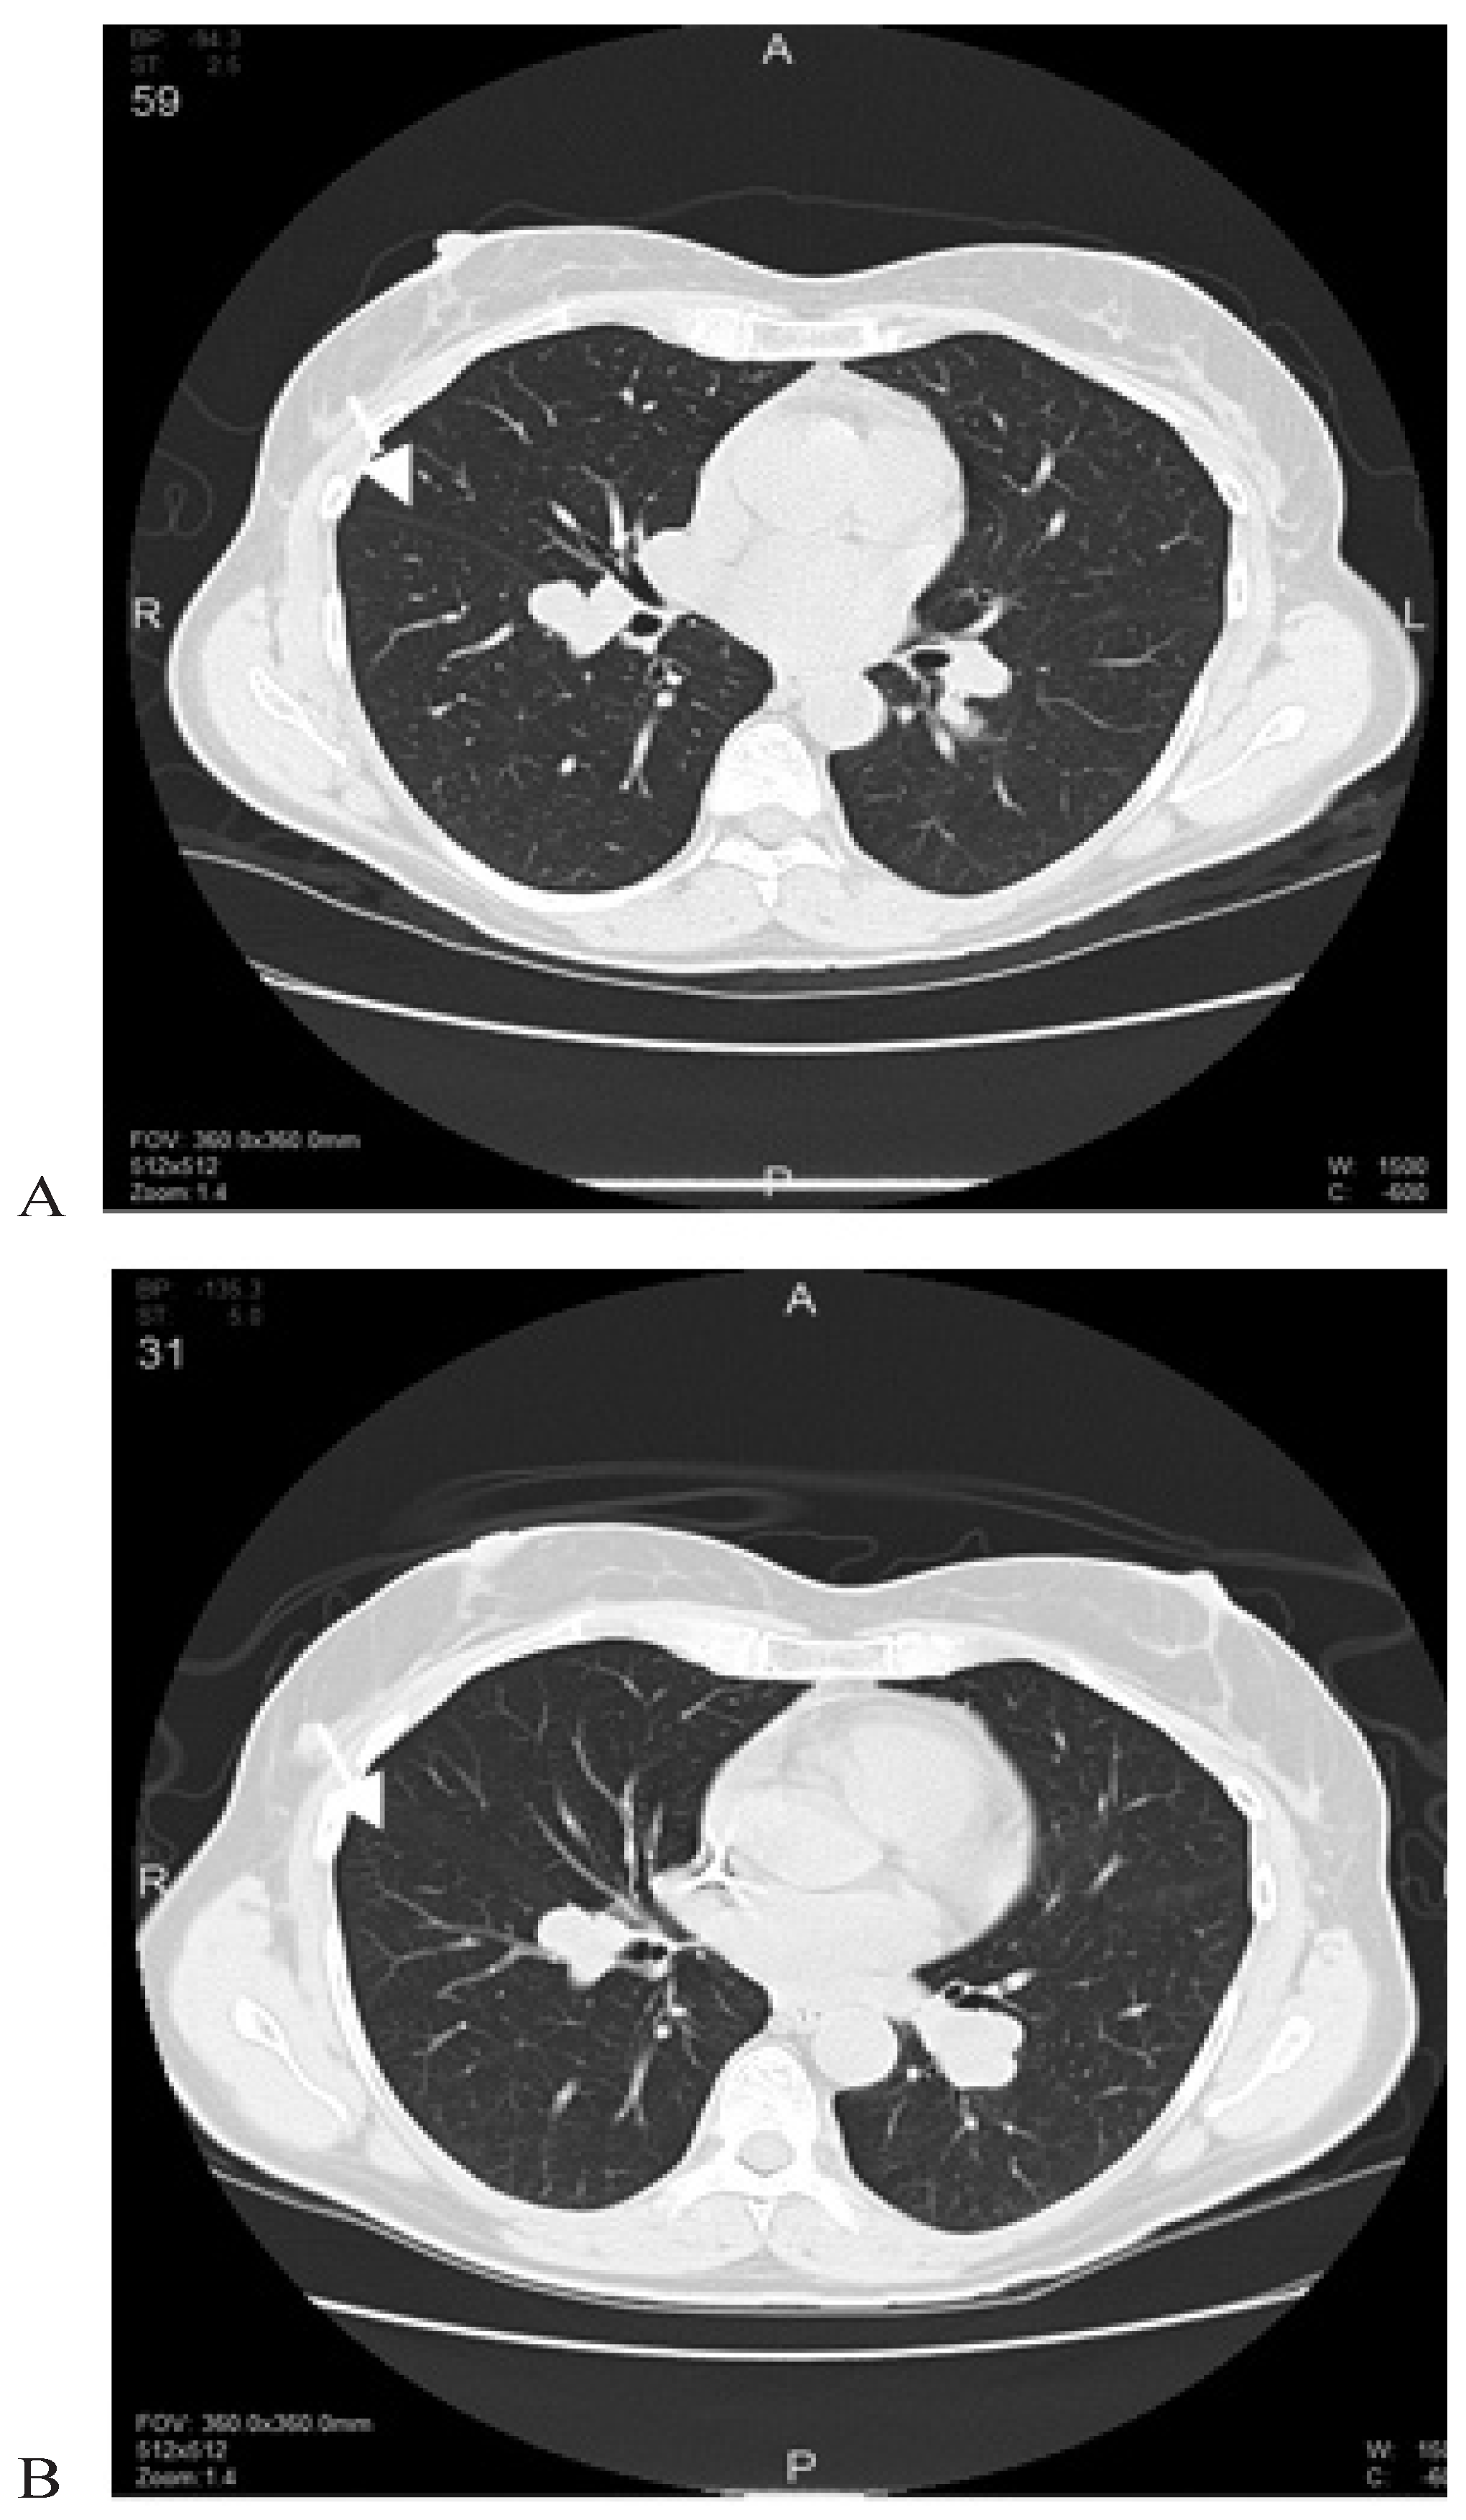

:1. CASE PRESENTATION